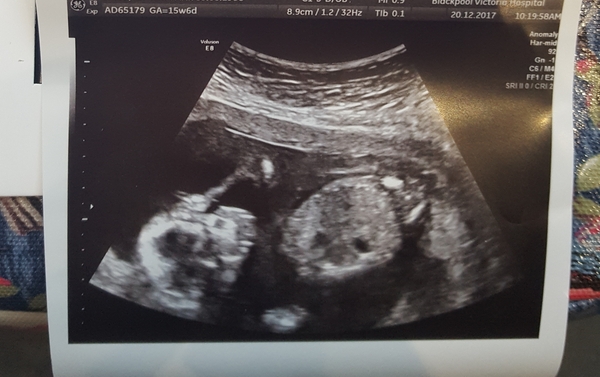

I just had my scan. Sonographer was happy with all the measurements and said everything looked present, but will be going over the chambers of the heart and everything again at the 20w scan. Rubbish pics cos kept on wriggling and looked like bubs was facepalming lol. Sonographer thinks its a boy 💙 Due date still 7th june, 15w 6d x

June 2018 #3